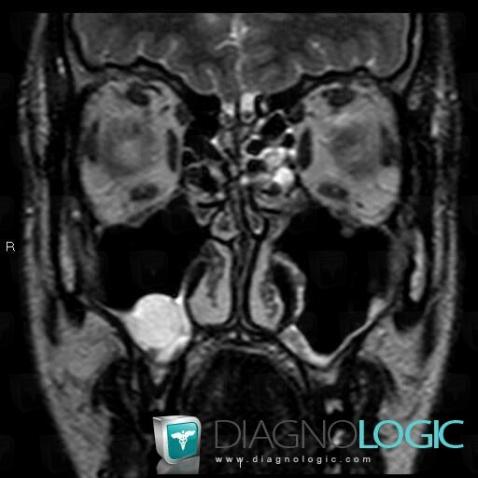

Les images ci-dessous illustrent ce dossier pour les diagnostics Kyste sous muqueux, pour les modalités (IRM)

Les gammes relatives à ce cas sont les suivantes : :

- Masse intra sinusienne

- Masse sinusienne de signal ou densité liquidienne

- Comblement sinusien

Voici les informations spécifiques à l'image clé ci dessus:

- Diagnostic Kyste sous muqueux, Localisation(s) Sinus, comportant les gammes Masse intra sinusienne, Masse sinusienne de signal ou densité liquidienne, Comblement sinusien